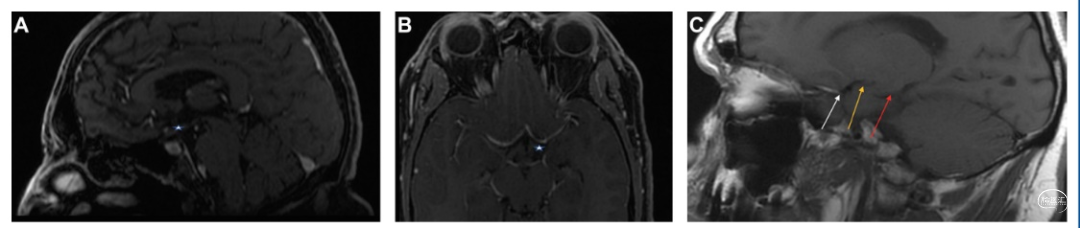

图1. 岛叶下界沟、颞干、中脑和OT的解剖。A. 显露MCA的M1-M3段、颞干和OT(从视交叉后方的OT起源点至LGB)的外侧和上方结构及大脑脚、大脑后动脉和小脑上动脉。B. 下外侧观:OT及其与脉络膜前动脉穿支的关系。C. 侧视图:蓝色表示颞干,白色表示视束后部与LGN相连处。D. 下视图:在切除OT的中间部分后,可见前上方的前穿质。AChAP,脉络膜前动脉穿支;APS,前穿质;FL,额叶;LGB,外侧膝状体;LGN,外侧膝状体核;MB,中脑;MCA,大脑中动脉;OC,视交叉;OT,视束;TS,颞干。

OT与钩回、尾状核、海马体和穹隆的位置关系:OT中段,在钩回上部走行,特别是杏仁核上方。后段(从下脉络膜点起)在尾状核尾部的内侧朝向后上方走行;其位于海马上方,其后侧部在接近LGN时则走行至外侧。此时,海马体呈内侧走行,通向胼胝体压部下方的胼胝体压部下回(图3)。

OT第二部分(即中段)的解剖位置关系:①在其上外侧为尾状核上束;②OT内上方为内囊最深纤维,在尾状核上束的上方呈头尾走向;③前连合在前述结构的前面,向两侧呈横向延伸。钩束(UF)和下额枕束(IFOF)在尾状核上纤维的上方和外侧。④在OT下内侧方向可见杏仁核的内侧部分、海马头部、下脉络膜点、AChA及其穿支(图4)。

图4. OT的外侧、内侧和上方区解剖结构。A. 在内侧,从前至后为前连合、尾状核上束和内囊深部;尾状核尾部上束纤维和内囊纤维朝向脑干走行。B. 从前方看OT上方和内侧的解剖关系。C. 红色指内囊,蓝色指尾状核上束,橙色指尾状核尾部的分叉,绿色指杏仁核。D. 侧位,分离OT和其紧邻的上部结构(尾状核束和纹状体苍白球区)。ACA,大脑前动脉;C,尾状核;IC,内囊;ICA,颈内动脉;MCA,大脑中动脉;OC,视交叉;OT,视束;SFC,尾状核上束;U,钩回。